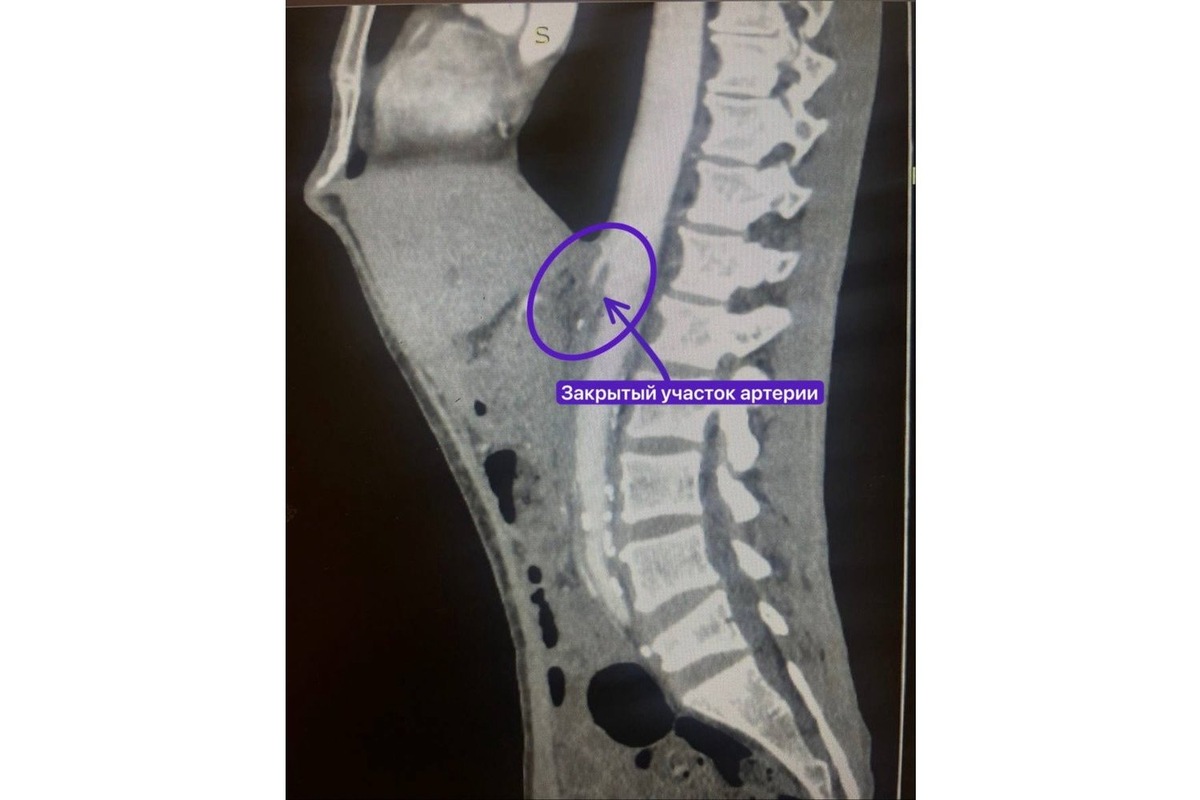

17 сентября пациент обратился в РКБ, где врачи сначала заподозрили панкреатит. Однако дальнейшее обследование показало, что причиной недомогания является серьезное нарушение кровоснабжения кишечника. Из-за атеросклероза бляшки практически полностью перекрыли верхнюю брыжеечную артерию.

Попытки рентген-хирургов установить стент в артерию оказались безуспешными из-за полной закупорки сосуда. Кишечник пациента продолжал функционировать только благодаря образовавшимся коллатералям — обходным путям кровотока.